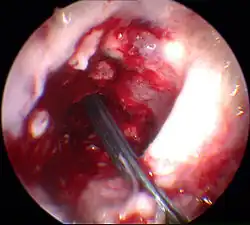

Élimination des restes de ligament croisé et percement des canaux osseux

Les restes du LCA rompu sont éliminés sous arthroscopie. Pour cela, on utilise un outil motorisé de découpe et d'aspiration. À l'aide d'un appareil à positionner, la position pour le percement d'un canal à travers la tête du tibia est déterminée, et le trou est fait. La même procédure est appliquée au percement à travers le fémur. Ce canal se rétrécit vers le haut et a une longueur d'environ 35 mm. La partie plus large de ce canal est destinée à recueillir le transplant, la partie étroite à faire passer l'accrochage du transplant.